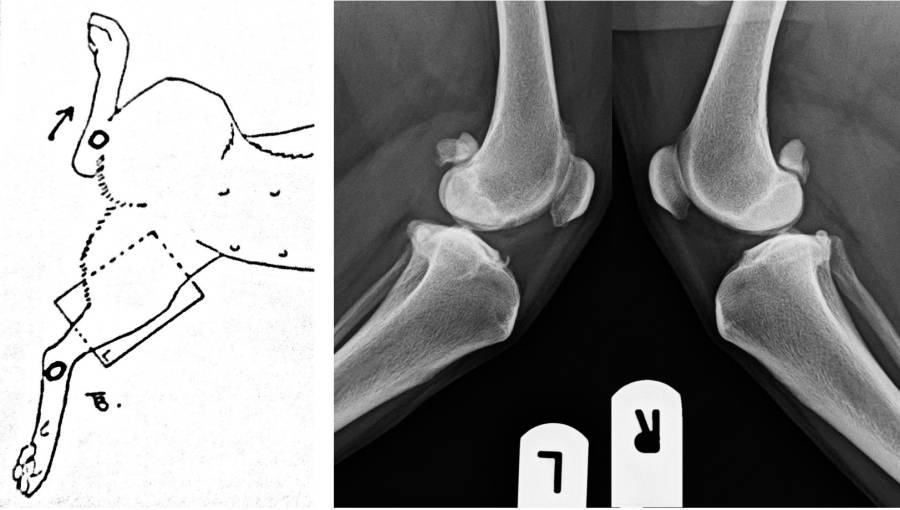

Röntgen Knie

- Vergleichende Aufnahmen: z.B. rechtes und linkes Knie